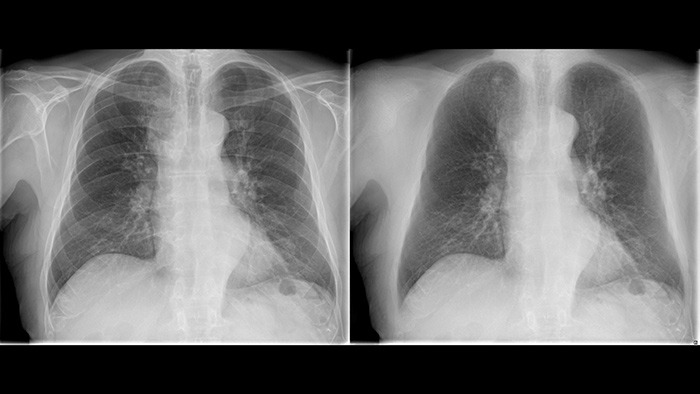

Philips UNIQUE 2 improves image quality with more homogeneous black backgrounds, reduced noise and automatic enhancement of small details

Philips Bone Suppression3 helps remove bone structures from chest images for an unobstructed view of soft tissue and can improve actionable nodule detection by up to 16.8% without the need to expose the patient to additional X-ray dose.4

Philips Bone Suppressionimproves actionable lung nodule detection up to 16.8%4